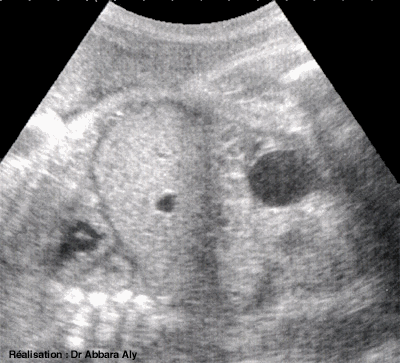

Diaphragme et coupe oblique

thoraco-abdominale